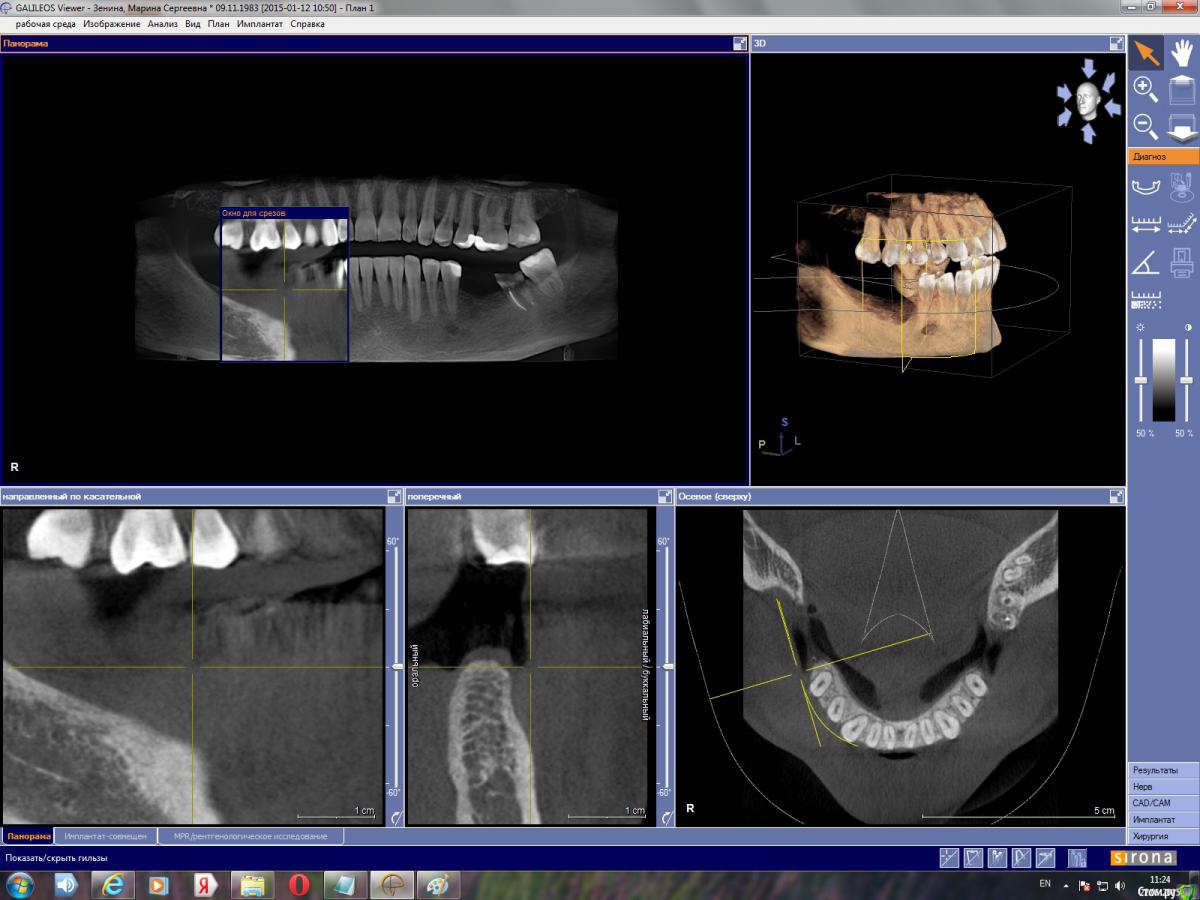

марин зенина Опубликовано 17 января, 2015 Автор Поделиться Опубликовано 17 января, 2015 https://yadi.sk/d/gpmuDkTXdwj3M архив моей КТ вместе с программой для просмотра GalileosViewer. Посмотрите, пжста, можно ли здесь обойтись без костной пластики. Ссылка на комментарий

марин зенина Опубликовано 21 января, 2015 Автор Поделиться Опубликовано 21 января, 2015 пожалуйста, подскажите нужно ли здесь наращивание кости) Ссылка на комментарий

Большой Зеленый Опубликовано 21 января, 2015 Поделиться Опубликовано 21 января, 2015 пожалуйста, подскажите нужно ли здесь наращивание кости)Нарежте скриншотов и выложите сюда.Никто не станет качать столько ненужной информации. Ссылка на комментарий

марин зенина Опубликовано 22 января, 2015 Автор Поделиться Опубликовано 22 января, 2015 выкладываю скриншоты) Ссылка на комментарий

марин зенина Опубликовано 22 января, 2015 Автор Поделиться Опубликовано 22 января, 2015 так? Ссылка на комментарий